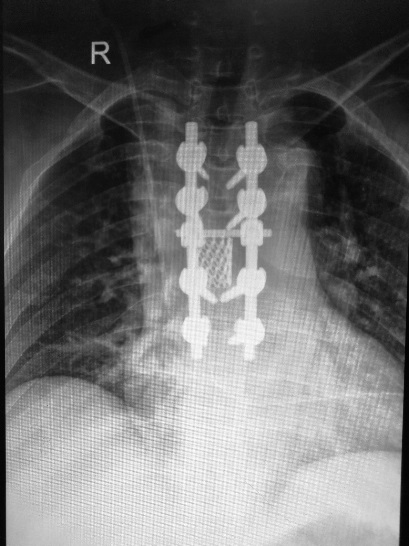

近期我科收治2名脊柱轉(zhuǎn)移性腫瘤的患者。2位女性患者突發(fā)胸背部疼痛及進(jìn)行性下肢無力,輾轉(zhuǎn)全國多家醫(yī)院,最終診斷為脊柱轉(zhuǎn)移性腫瘤。因腫瘤侵入椎管,治療難度高,遲遲未得到手術(shù)治療。經(jīng)人介紹來我院就診,為解除患者痛苦,主管醫(yī)生裴海波對病人詳細(xì)查體及全方位檢查后匯報(bào)張富軍主任,經(jīng)科室討論后,為患者制定了周密的手術(shù)方案—全脊椎整塊切除術(shù),并順利實(shí)施。

我院骨科在張富軍主任帶領(lǐng)下,李靖教授的指導(dǎo)下,分別于2017年9月1日和2017年9月29日順利為2位患者行全脊椎整塊切除手術(shù)。手術(shù)平均時(shí)間3個(gè)半小時(shí),手術(shù)過程順利,均按照術(shù)前計(jì)劃成功將椎體整塊切除,未出現(xiàn)手術(shù)并發(fā)癥,術(shù)后恢復(fù)良好。